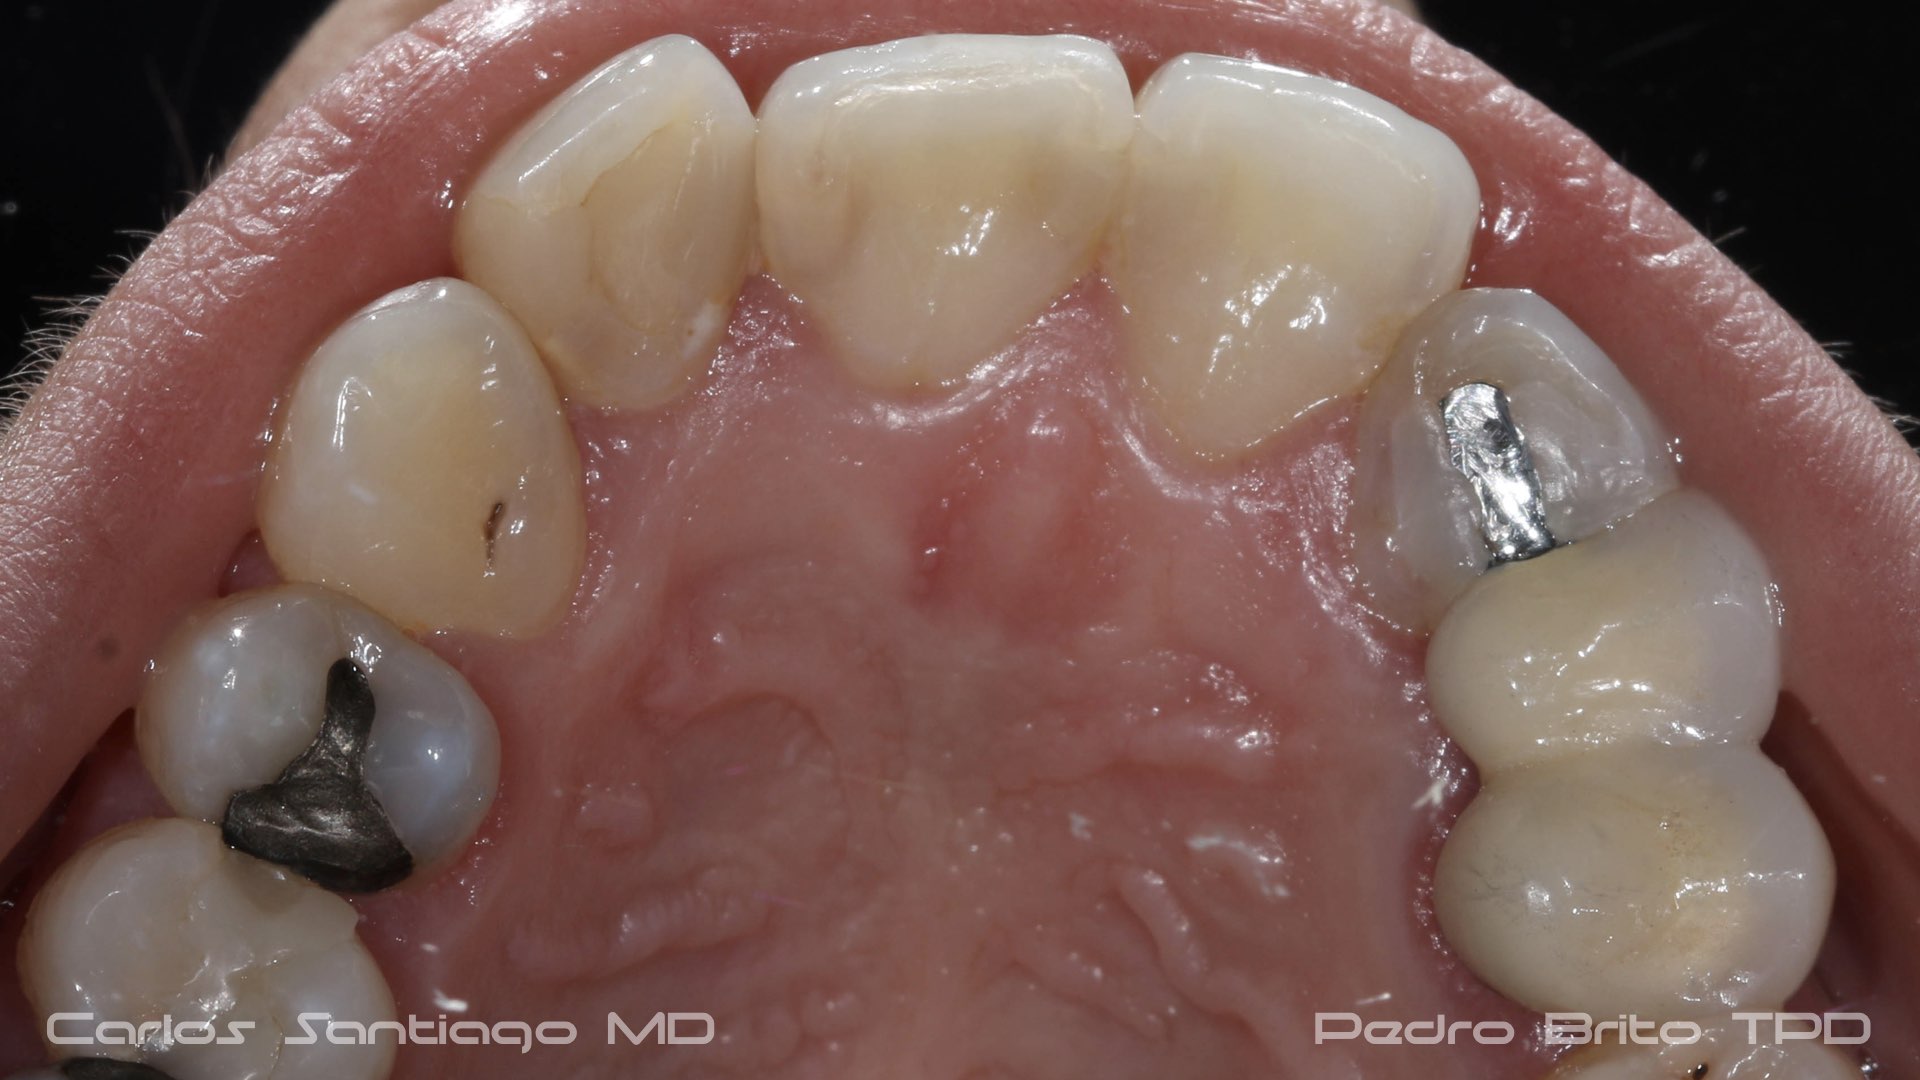

As Facetas Cerâmicas (lentes de contacto dentárias ou laminados), permitem corrigir da maneira mais estética e conservadora possível, problemas de forma e tamanho, côr e posição dos dentes, bem como substituir restaurações antigas e inestéticas.

São aderidas químicamente ao esmalte dentário de uma forma permanente, com o objectivo de melhorar a estética dos nossos pacientes.